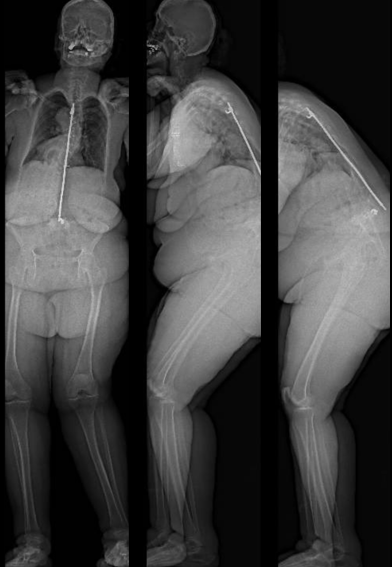

From robotics and AI-driven surgical planning to virtual modeling and custom implants, I’ve embraced a combination of tools that allow me to create tailored surgical plans for my patients—particularly those with scoliosis and spinal deformities.

What sets my approach apart is the seamless integration of these advanced technologies to ensure unparalleled accuracy and better outcomes for each patient.